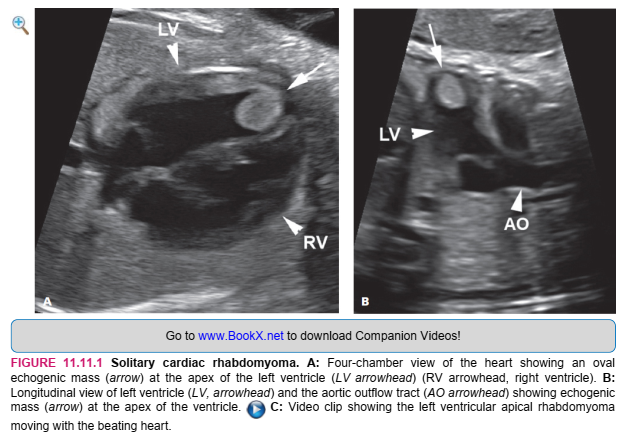

Tumors of the myocardium are most often rhabdomyomas, which, when multiple, are usually a manifestation of tuberous sclerosis. Rhabdomyomas are hamartomas of cardiac muscle that arise in the myocardium and tend to grow during gestation. Cardiac failure with hydrops in utero may result from either obstruction of blood flow by the rhabdomyoma or poor cardiac contractility due to replacement of normal myocardium by tumor. The prognosis for cardiac rhabdomyomas is related to the size and number of rhabdomyomas. If hydrops develops in utero, the prognosis is worse than in the absence of hydrops. After birth, cardiac rhabdomyomas occasionally regress.

SONOGRAPHY

Cardiac rhabdomyomas are visible as round or oval masses arising from the myocardium. They are typically more echogenic than normal cardiac muscle, and they may be single (Figure 11.11.1) or multiple (Figure 11.11.2). When hydrops is present, pericardial fluid may outline the myocardial tumors.